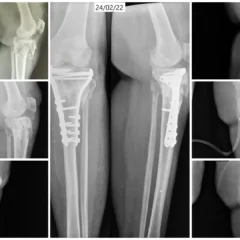

Clinical examination and imaging studies confirmed a Right Proximal Tibia Fracture involving both medial and lateral columns of the bone. Such fractures require precise anatomical reduction to restore joint alignment and maintain knee stability.

Open Reduction and Internal Fixation (ORIF) with Bicolumnar Plates and Screws

Mrs. Ananthamma underwent Open Reduction and Internal Fixation (ORIF) using bicolumnar plates and screws.

Anatomical realignment of both medial and lateral columns

Stabilization using dual (bicolumnar) plating technique

Rigid fixation with screws for enhanced stability

Bicolumnar fixation provides superior mechanical strength, especially in complex fractures involving both sides of the proximal tibia.